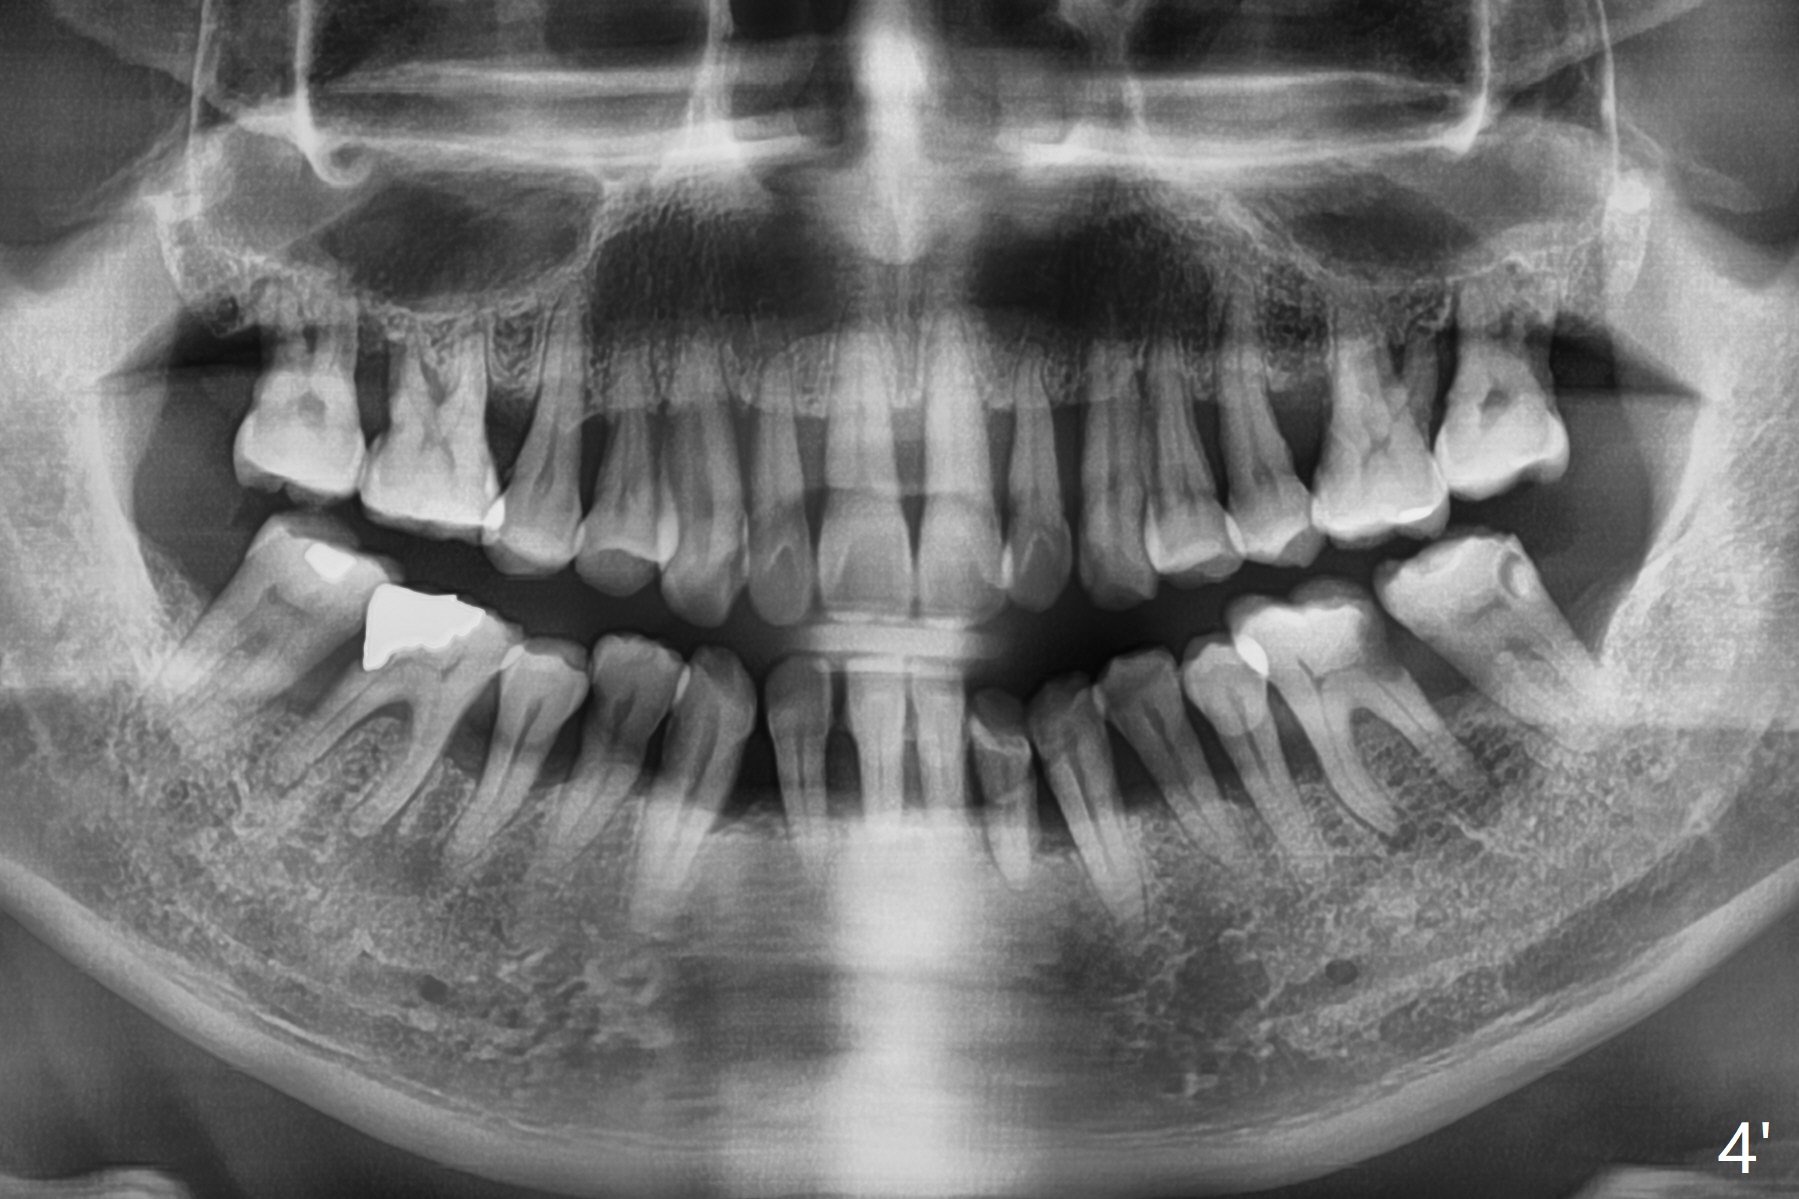

A 60-year-old man with large DO amalgam at #30 develops pain and mild swelling apparently apical to #29.  Both teeth (having fused PARL (periapical radiolucency) *) have mild percussion with the tooth #29 having higher mobility.  CBCT shows apical defect (Fig.3 >).  Three weeks earlier, the tooth #19 had much more severe infection (Fig.4') with a similar apical defect (Fig.4 >).  Combined with history of repeated infection associated with #30, the tooth is extracted.  Because of severe infection it is difficult to obtain sound anesthesia.